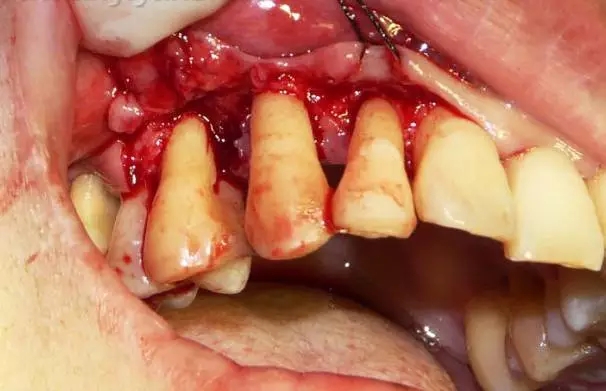

翻開頰側(cè)粘骨膜瓣,牙石沒有了但是還有大量的肉芽組織

這張圖片是去除肉芽組織之后的圖片,我們看到右上五的近中面還有一條黑色的牙石存在,這是三次齦下刮治后遺留下來的牙石,由此可見,對于重度牙周病僅僅靠齦下刮治是無法徹底清除齦下牙石的,牙周手術(shù)治療還是非常有必要的。